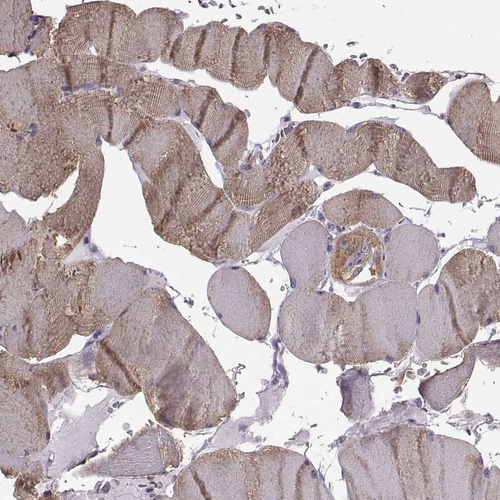

Immunohistochemistry analysis in human skeletal muscle and heart muscle tissues using Anti-JSRP1 antibody. Corresponding JSRP1 RNA-seq data are presented for the same tissues.